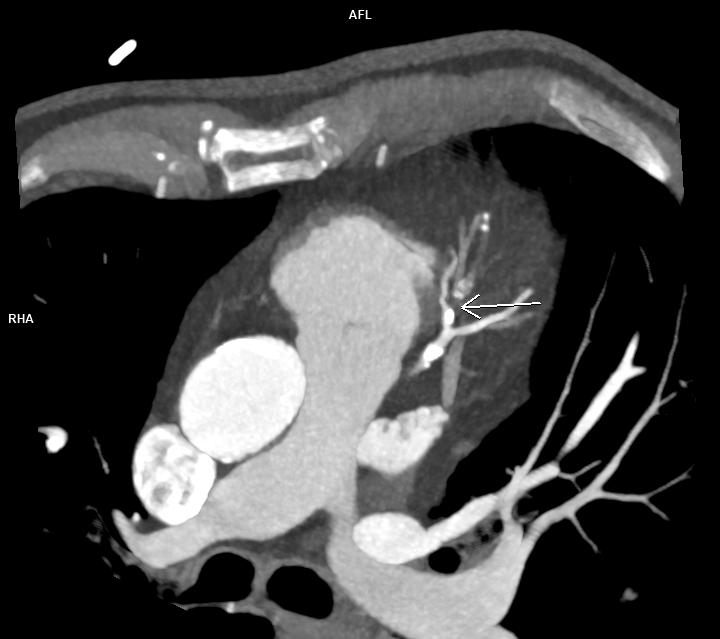

Figura 1: reconstrucție mutiplanară MIP din achiziție angioCT coronariană cu sincronizare ECG

Discuţie caz nr 120: Achiziția angioCT coronariană cu sincronizare ECG evidențiază ocluzie a arterei descendente anterioare în segmentul mediu cu hipokinezie severă / diskinezie a miocardului deservit și formarea unui anevrism antero-septal și apical ventricular stâng ce este locuit de un tromb.